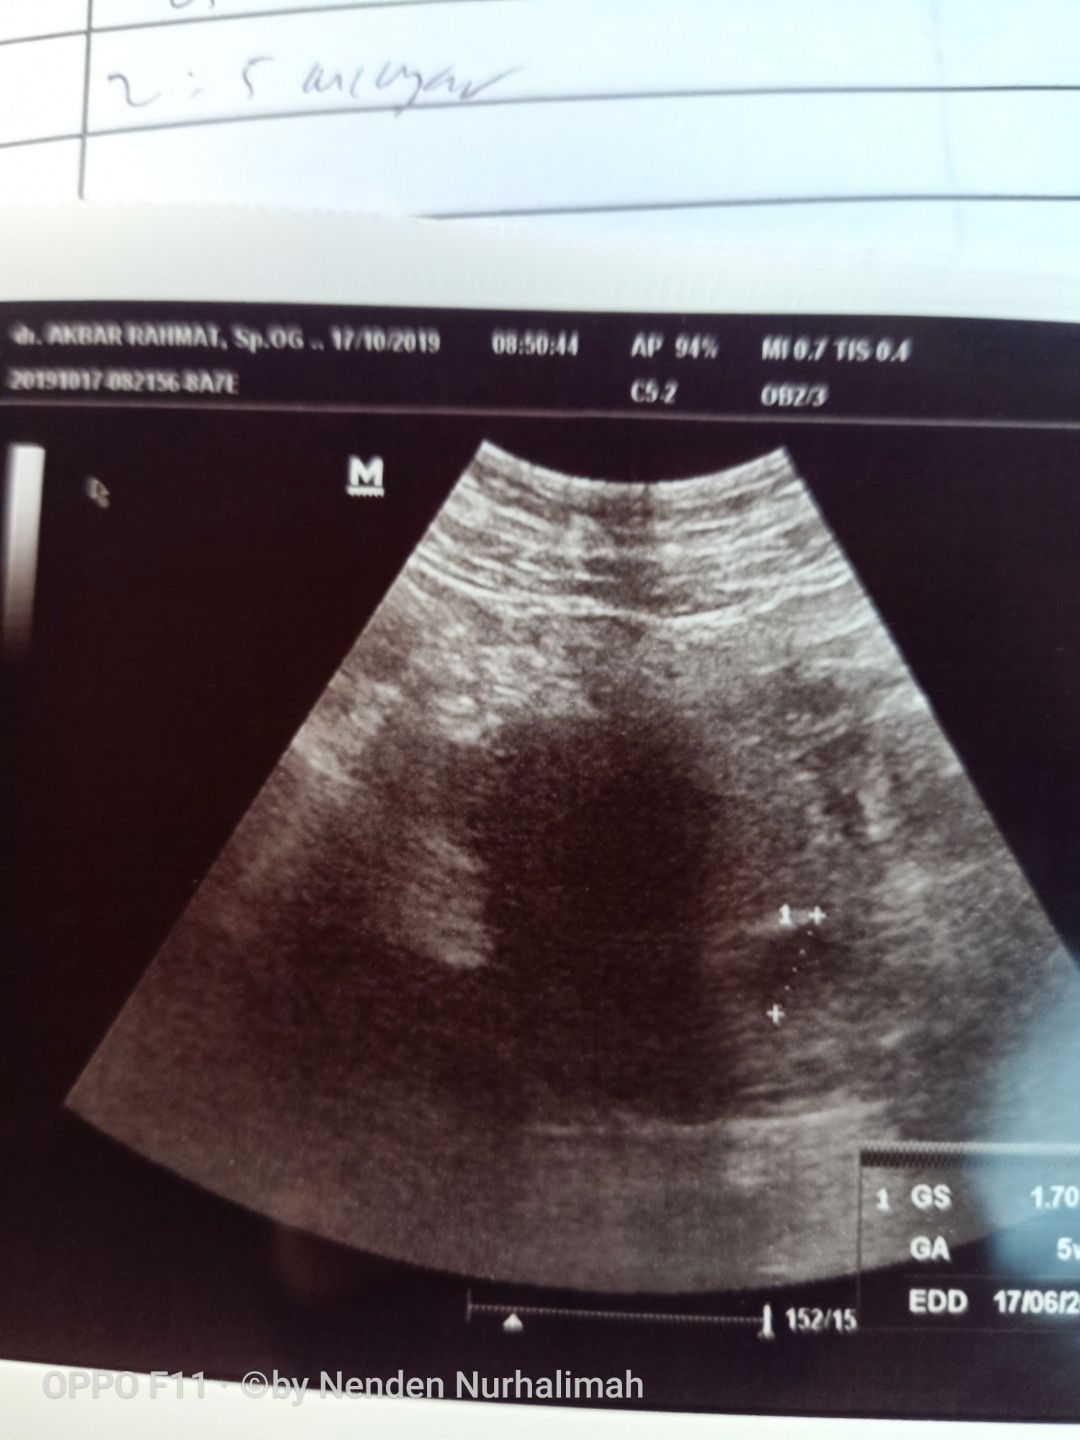

USG

Selamat pagi bunda,, saya awal periksa k bidan katanya udah 4 minggu bulan lalu itu berarti kalau d hitung sekarng udah 8minggu,, eh pas di USG dokter bilang baru 5 minggu